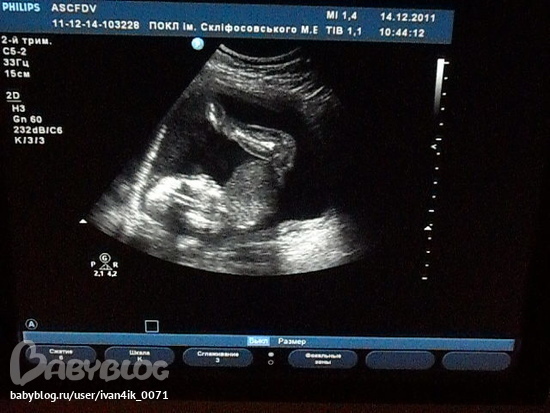

Как здорово!!Когда же мы уже так заумеем на УЗИ,дождаться не могу,на малышика посмотреть,но ничего осталось чуть-чуть))